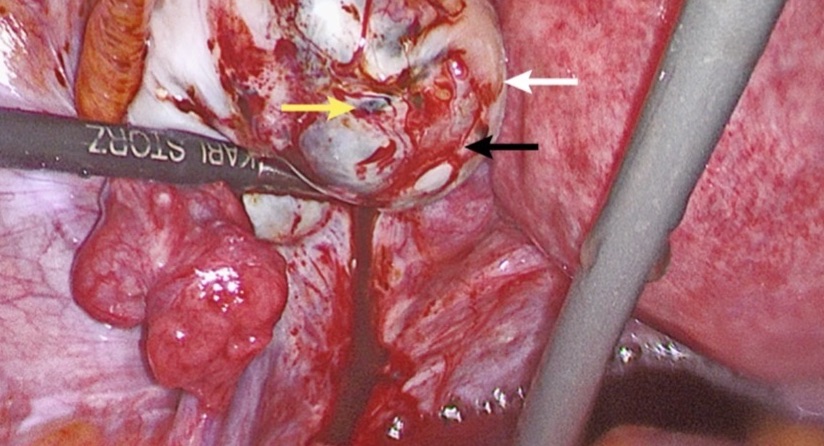

Endometriosis is defined as the presence of endometrium-like tissue, i.e. the uterine lining, outside the uterus. In the vast majority of cases endometriotic tissue (lesions) are found in the abdomen, in particular in the pelvis of women. Only rarely endometriosis is found in other areas of the body. The abdominal lesions can be singular or multiple, have different colours (mostly red, clear, brown, black/blue or white), and lie superficially or invade deeper tissues or surrounding organs. Currently most people assume that three different types of abdominal endometriosis exist:

- Ovarian endometriotic cysts (also known as endometriomas or ‘chocolate cysts’)

Endometriosis is a mostly intra-abdominal disease and lesions can be identified during surgery. Today, surgery should generally consist of a laparoscopy (‘key hole surgery') as opposed to an open (laparotomy) procedure due to better vision and faster post-operative recovery. Endometriosis identified visually should ideally be confirmed by histology. However, if no endometriosis can be identified under the microscope the condition is not fully ruled out.